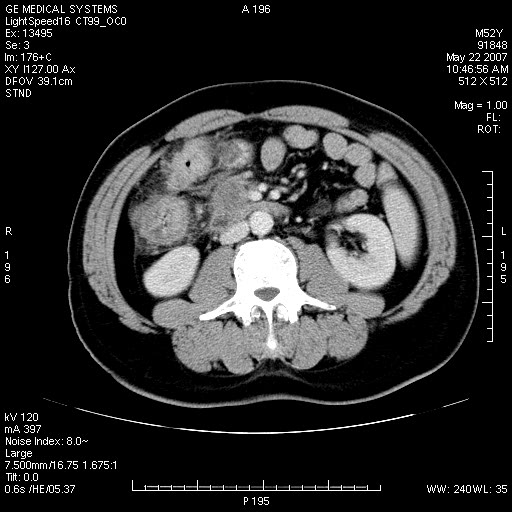

以下是引用余辉在2007-5-22 20:12:00的发言:[br]升结肠管壁明显增厚,增强有静脉期持续增强,结合患者病史,考虑结肠癌可能性大,临近脂肪影密度增高,混浊,恐有肠系膜浸润转移,建议镜检

以下是引用dyqct在2007-5-22 20:43:00的发言:[br]支持结肠肝曲占位性病变(浸润型结肠癌可能性大)。胆总管下端扩张,原因待查。

以下是引用gaoxiao在2007-5-22 20:49:00的发言:[br]考虑升结肠癌向周围侵犯,胰头钩突受侵。